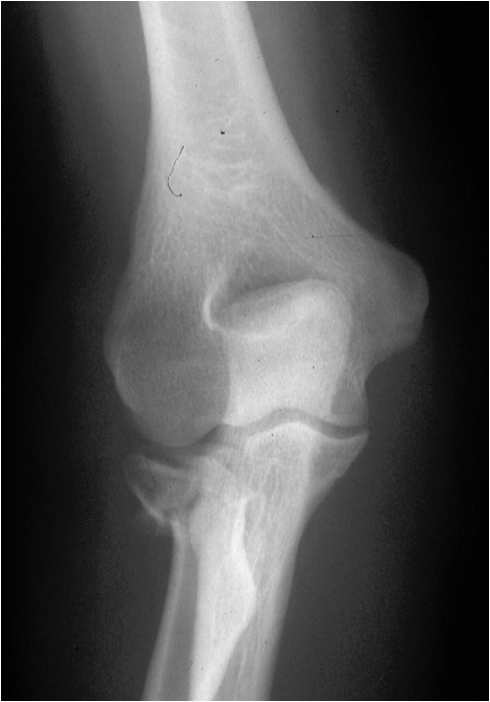

The radial head is a round disc of bone with cartilage cap which articulates with the humerus as part of the elbow joint.

Radio-capitellar Osteoarthritis – This sounds complex but just means arthritis between the radial head and the capitellum on the outside of the elbow (see illustration at top of page!) This condition is characterised by the findings on an xray of reduced joint space from loss of cartilage in the joint. It is usually asymptomatic, but can give rise to pain from the joint around the outside of the elbow.